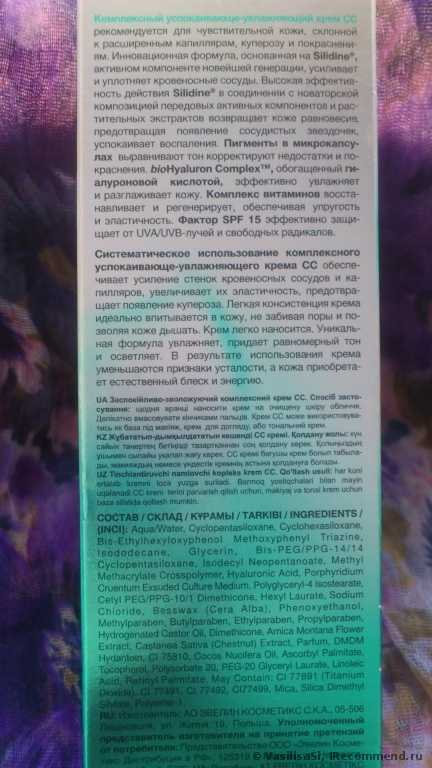

Летом моя кожа особенно склонна к покраснениям и купероз (сосудистые звездочки и расширенные капилляры) становится более выраженным. Я вообще не загораю, использую сонцезащитные кремы и ношу шляпу с полями.

Когда мне понадобился легкий сонцезащитный крем для лица на лето, то в первую очередь я подошла к полкам с «Eeveline cosmetics», потому что это одна из любимых мной марок. Мое внимание привлек этот крем, потому что производитель обещает уменьшение купероза, увлажнение и смягчение кожи, защиту от УФА и УФБ лучей (SPF 15), коррекцию тона и мелких недостатков. Все эти обещания были кстати для летнего ухода. Крем не дорогой (142 руб), поэтому рискнула попробовать, не особо вчитываясь в состав. Дома вскрыла упаковку и познакомилась к кремом поближе.

Крем оказался нежной консистенции и бледно-зеленого цвета, с темными микро-капсулами пигментов. Зеленый тон всегда используется для маскировки покраснений. Запах легкий, травянистый, нейтрально ароматный.

При нанесении на кожу он легко распределяется без липкости или жирности. Действительно при растирании крем теряет свой зеленый оттенок и кожа приобретает цвет легкого загара (чем сильнее я растирала, тем темнее получался «загар»). Расширенные сосуды он слегка маскирует, тон кожи выравнивает. Если наносить крем специальным спонжем для тонального крема, то он ложится ровно тонким слоем, не приходится растирать и поэтому оттенок остается очень светлым, так лучше маскируются сосудики и покраснения. На лице крем не ощущается, эффекта маски нет. Не рекомендую наносить крем толстым слоем или в несколько слоёв, потому что при повторном растирании ранее нанесенного крема оттенок станет более темным. Я наношу крем один раз и хожу с ним весь день, кожа выглядит естественно, неприятных ощущений нет, вообще его не замечаю. Вокруг глаз его наносить нельзя, для этого я приобрела специальный крем для век Eveline с УФ защитой.

Одной тубы (30 мл) мне хватило почти на 2 месяца. За это время я заметила, что сосудики стали менее выраженными и краснота уменьшилась. Кожа разгладилась, уменьшились морщинки. Крем обладает матирующим эффектом и я перестала пользоваться пудрой. Правда в течении дня появляется легкий лоск, для снятия которого прикасаюсь слегка к лицу бумажной салфеткой.

Конечно для достижения более выраженного эффекта нужно больше времени, поэтому вчера купила новую упаковку крема, буду пользоваться все лето, о результатах сообщу. Крем достаточно стойкий, с минеральными пигментами, поэтому вечером убираю его мицеллярным раствором Eveline. На ночь тонким слоем наношу «Активный отбеливающий крем» Eveline. На фото видно, что в целом кожа стала светлее, пигментные пятна уменьшились. Днем пигмента не прибавляется благодаря сонцезащитным свойствам крема СС, а ночью кожа осветляется под действием отбеливающего крема.

Что касается состава, то крем действительно содержит экстракты лекарственных растений и витамины (см. в «Подробностях»), но они в самом конце списка ингредиентов, после 4 парабенов, касторового и кокосового масел), а в начале списка (первые 10 позиций) после воды значатся различные натуральные и синтетические эмоленты (вещества смягчающие и увлажняющие кожу, облегчающие распределение и нанесение крема). Поэтому одну звезду снимаю.

Подведем итог.

Плюсы:

- Крем действительно работает.

- Успокаивает и увлажняет кожу.

- Уменьшает красноту и купероз.

- Выравнивает тон кожи и корректирует недостатки.

- Защищает от УФА и УФБ лучей.

- Легко наносится.

- Нет «эффекта маски».

- Достаточно стойкий, с минеральными пигментами.

- Благодаря гиалуроновой кислоте, разглаживает кожу и уменьшает морщинки.

Минусы:

- В начале использования, когда покраснения и купероз сильно выражены, маскирует не достаточно хорошо (это ведь не тональный крем и маскировка несовершенств его дополнительный эффект, а не основной).

- При нанесении толстым слоем или в несколько слоёв тон может получиться слишком темный и неровным.

- Много химии в составе (куда же без неё?).